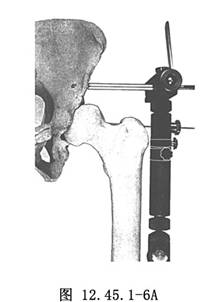

6.用“T”形扳手將皮質骨半徑針擰入髂骨,當感覺突破內板後,再擰入6個半圈(圖12.45.1-6A)。接下來擰入第2根半徑針(圖12.45.1-6B)。通常髂骨應用2根半徑針已經足夠,但也可擰入第3根,以進一步增加穩定性。